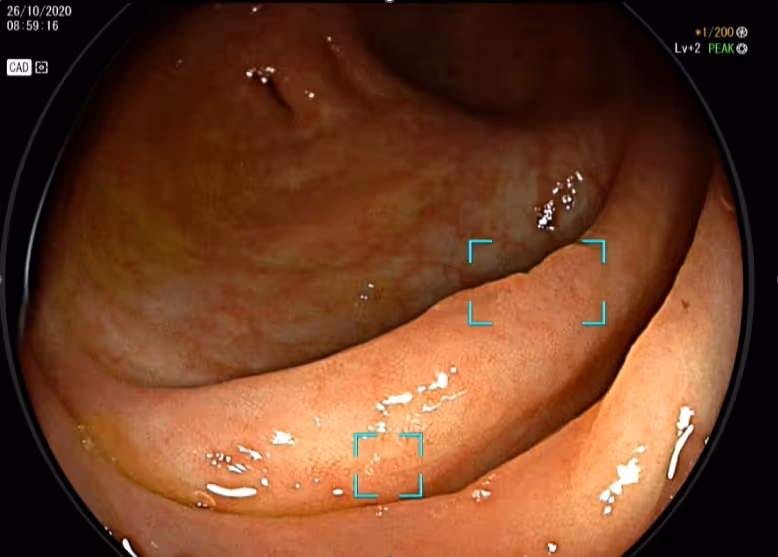

ตัวอย่างการส่องกล้องด้วย DEEP GI ที่มีเทคโนโลยี AI ช่วยแพทย์ตรวจจับและแจ้งเตือนเมื่อพบติ่งเนื้อที่เป็นอันตราย

สำหรับการส่องกล้องลำไส้ใหญ่ ศูนย์ทางเดินอาหารและตับ โรงพยาบาลเมดพาร์ค ได้มีการนำนวัตกรรมที่ชื่อว่า DEEP GI มาเป็นผู้ช่วยแพทย์ในการวิเคราะห์และแจ้งเตือนเมื่อพบติ่งเนื้ออันตรายในขณะทำการส่องกล้องได้แบบเรียลไทม์ มีความแม่นยำสูงถึง 90% ถือเป็นเทคโนโลยีระบบปัญญาประดิษฐ์ (AI) ที่ช่วยคัดกรองโรคมะเร็งลำไส้ใหญ่ได้อย่างมีประสิทธิภาพ